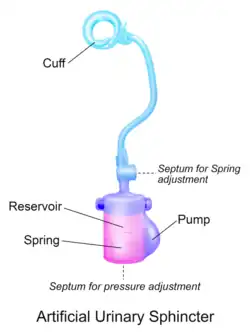

- The artificial urinary sphincter with a spring (2-component): cuff and pump unit.[3][4] The cuff is placed around the urethra and the pump unit is inserted in the scrotum. The pressure in the hydraulic circuit is generated by the spring of the pump unit. The pressure in the retropubic space does not have any influence for this type of sphincter.

Another AUS model is the ZSI 375 (Zephyr Surgical Implants, Geneva, Switzerland), introduced in 2008.[11] It is a one-piece two-part device with a cuff and a pump unit with an integrated spring; it comes in one piece, pre-connected and pre-filled.[1][12] There is no abdominal component in the ZSI 375, which along with its ready-to-implant configuration reduces the operating time.[13] Furthermore, because there is no abdominal component, surgical interventions in the retroperitoneal space are not required. Previous surgeries, such as radical prostatectomy, may lead to post-operative scarring and fibrosis in the retroperitoneal space. Thus, avoiding dissection of retroperitoneal tissues avoids risks of surgical complications.[14][15] Another advantage of the ZSI 375 model is the possibility to increase or decrease the pressure inside the device after implantation to meet the desired continence rate and satisfaction of the patient. These adjustments particularly help to control continence in cases of post-implantation urethral atrophy or urinary retention (poor urine flow).[16][17][13] Adjustment of the pressure can be done in an outpatient setting by adding or removing sterile saline solution via a syringe through the scrotum.[12] By 2019, more than 4,500 ZSI 375 artificial urinary sphincters have been implanted worldwide.[11] In addition to the devices mentioned above, new devices are being brought to market, such as the Rigicon ContiClassic and ContiReflex Artificial Urinary Sphincter systems. [18][19]